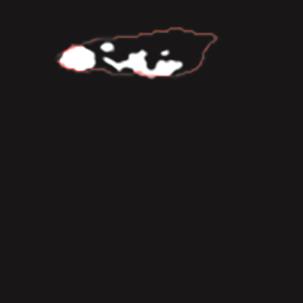

乳腺癌是全球女性最常见的恶性肿瘤之一,准确的病变分割对于乳腺癌的早期诊断与治疗具有重要意义。然而,由于病变形态的多样性以及超声成像机制的复杂性,现有基于深度学习的乳腺超声图像病变分割方法在分割准确性方面仍面临巨大挑战。为进一步提升乳腺超声图像中病变区域的分割精度,该文基于经典U-Net架构,提出了一种新型乳腺超声图像病变分割网络(CWSASKM-BBAM-Net)。首先,在网络中引入逐通道空间自适应选择核卷积模块(CWSASKM),根据不同通道的语义特征为每个空间位置自适应选择感受野大小,以增强多尺度信息的建模能力;然后,引入双向边界感知机制(BBAM),通过融合正向与反向注意力,对目标显著区域及其边界进行协同建模,同时逐步提升对非显著区域与病变区域的区分能力,以进一步强化边界信息的表达;最后,在3组公开乳腺超声图像数据集(BUSI、UDIAT和STU)上开展分割实验。结果表明:该方法在数据集BUSI上的杰卡德指数、精确率、召回率和Dice相似系数分别为71.97%、82.85%、81.40%和80.44%,较次优方法分别提升1.69、1.05、1.28和1.84个百分点;在数据集UDIAT上,这4项指标分别达到78.14%、88.31%、86.73%和86.10%,较次优方法分别提升了2.75、2.04、0.56和2.01个百分点;在外部数据集STU上,该方法也取得了优于其他方法的整体表现。实验结果表明,CWSASKM-BBAM-Net在乳腺超声图像分割任务中展现出更优的整体性能。